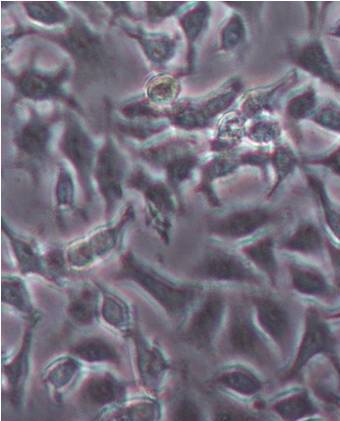

Cell migration

In this study, the U-87 MG cells were examined for the effect of drug on cellular migration and the results are illustrated in the following fig 12. The GCB loaded MPEG-PCL nanoformulation (GCBNP 3) treatment resulted in a significant inhibition of cell migration.

Invasion assay

The GCB loaded MPEG-PCL nanoformulation (GCBNP 3) showed a significant drop in the ability to migrate into the empty space compared with control in U-87 MG cells and the number of cells crossed matrigel in the drug treatment was significant decreased compared to the control cells.

Invasion images of the plain drug, PNP and GCBNP 3 in U-87 MG cell lines are shown in fig. 13.

Fig. 12: Inhibition of cell migration by control, pure drug, PNP and GCBNP 3 in U-87 MG cell lines